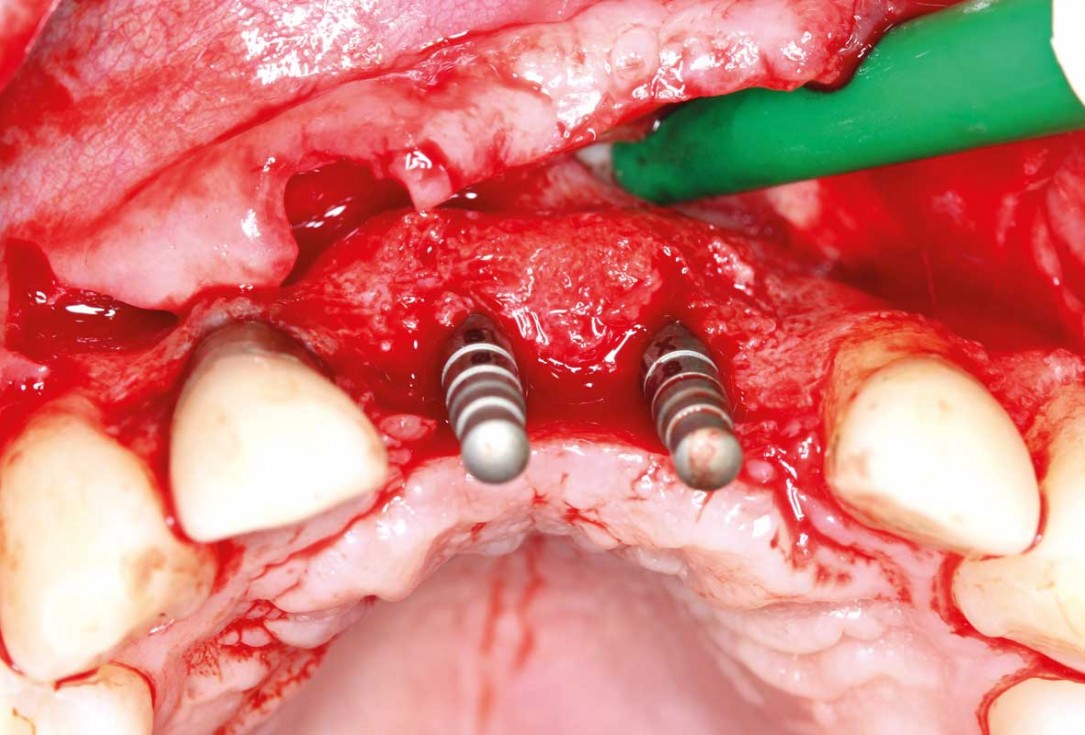

14/26 - Insertion of two Straumann BLX implants 3.75 x 14 mm / 3.75 x 12 mm

Ridge augmentation in the maxilla with maxgraft® bonebuilder in the aesthetic zone - Dr. M. Kristensen